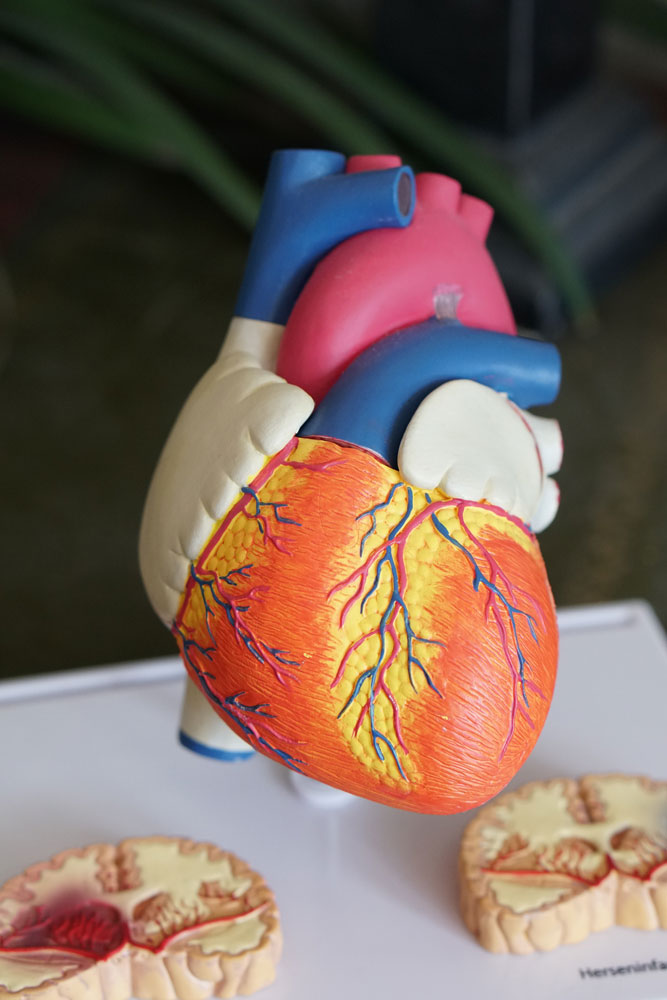

Having a heart disease is not something that you can ignore. You need to take care of your heart by following some steps. There are many ways through which you can get the treatment for your heart disease, but one of the good ways is to consult with cardiologists in Sydney. They are experts who will help you understand about your condition and then provide you with the best possible treatment plan.

Cardiologists Sydney is a good place to go if you need to find a cardiologist. Cardiologists are doctors who care only about the heart and its diseases. Heart specialists in Sydney will be able to help you with all your heart problems, whether it is high blood pressure or stroke. Heart diseases are very common in Australia, so if you have any problems with your heart it’s best to get help from a specialist as soon as possible before it gets worse. You can find many types of specialists most especially when looking for a Cardiologist in Sydney because there are many hospitals that offer this type of service but one thing that’s important is finding someone who can give quality service which means finding someone who has years of experience working with patients.

Cardiologists in Sydney are experts in the heart. They can help you understand your heart health and manage your condition. Cardiologists specialize in preventing, treating and managing cardiovascular conditions, including heart attacks, stroke, high blood pressure and arrhythmias (irregular heartbeats). Cardiologists can also provide support for patients living with congenital heart disease or who have experienced a ventricular assist device (VAD) implantation or cardiac surgery.

Cardiologists are experts in heart health and can diagnose and treat many common diseases. They are train to treat a wide range of heart conditions including:

A heart specialist Sydney is someone who has been trained in the diagnosis and treatment of heart disease. They are able to do a variety of tests to determine what’s causing your symptoms, including an electrocardiogram (ECG), Holter monitor test, stress echo test or cardiac CT scan.